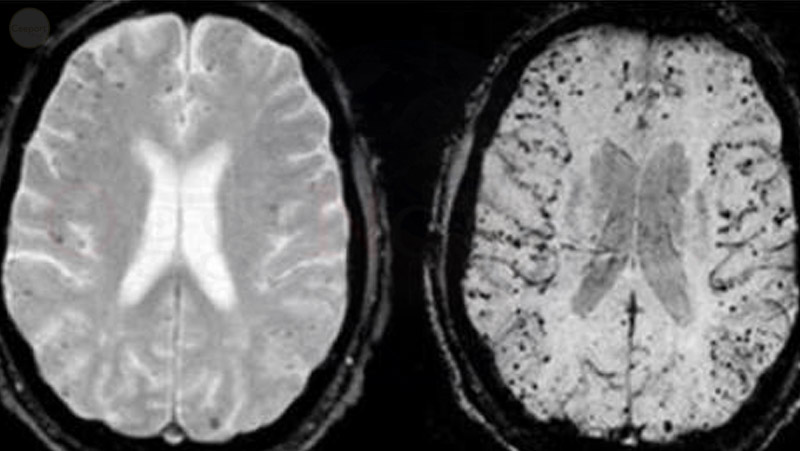

Uno dei motivi principali per cui questo accade è perché l’alluminio viene accumulato nelle regioni specifiche del cervello che sono più sensibili ai danni nella malattia di Alzheimer. Molti studi hanno inoltre dimostrato che l’alluminio porta alla formazione anormale di placche beta-amiloide nel cervello dell’animale. Queste placche vengono creati non appena beta-amiloide, o le parti di proteine adesive, si raggruppano e ostacolano cellula-cellula segnalazione alle sinapsi. Inoltre, attivano le cellule del sistema immunitario che stimolano l’infiammazione e divorano cellule disabili. Questo processo avviene nelle stesse regioni del cervello in entrambi gli animali e le persone.

esposizione alluminio provoca l’ennesimo cambiamento neurologico che è tipico per i pazienti affetti da morbo di Alzheimer. Essa provoca la formazione di grovigli neurofibrillari – collezioni anormali di fili ritorti proteine nelle cellule nervose che sono principalmente fatti di una proteina.Questi grovigli anche ostruiscono i neuroni di comunicare tra loro, che è una manifestazione tipica del morbo di Alzheimer.